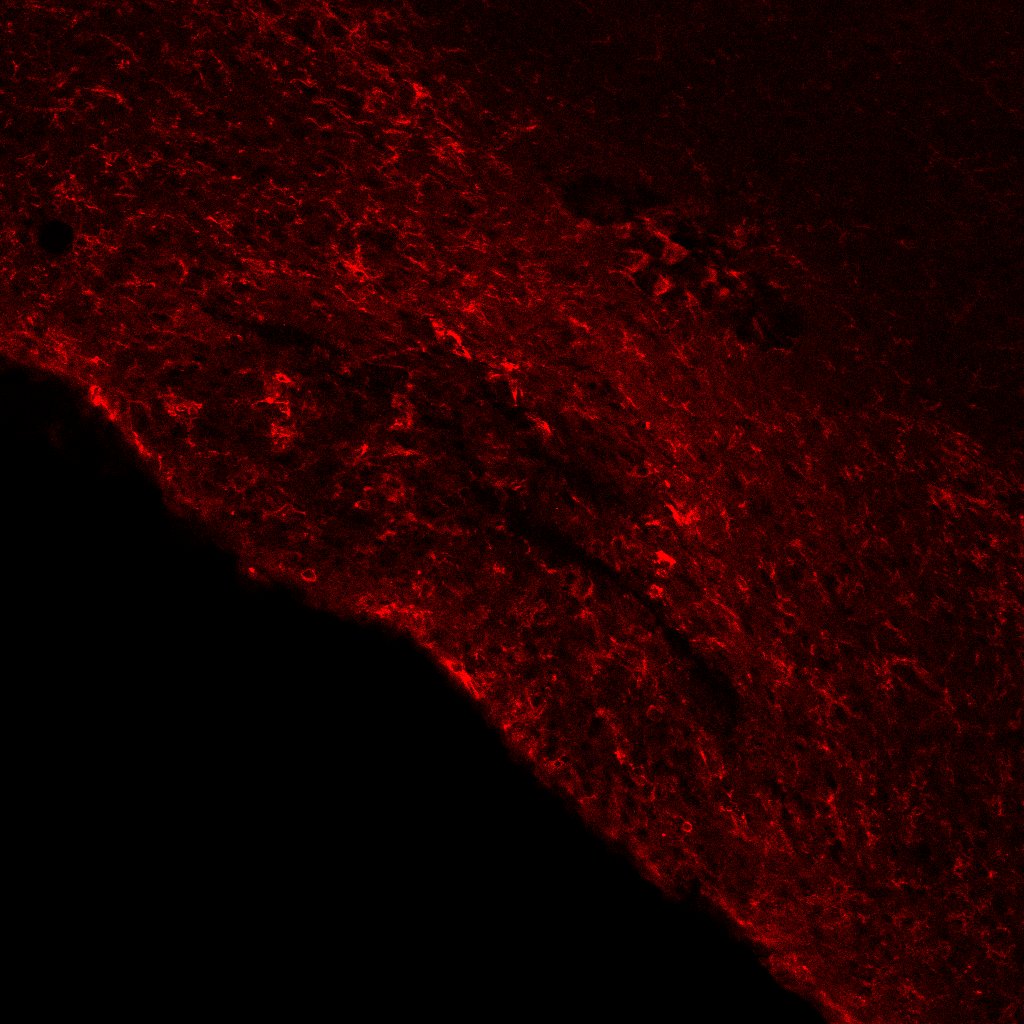

FH Sama (Verified Customer) (03-26-2026) | Did not stain as expected :( Expected staining of ependymal cells, but staining did not look like ependymal cells

![]() |